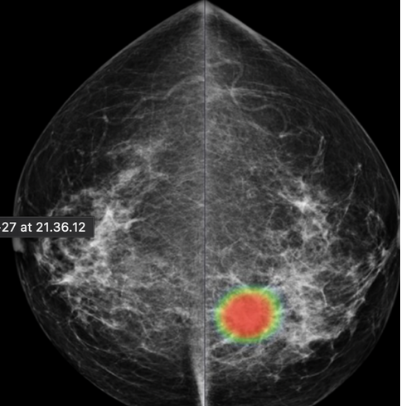

DAM - Breast Solution

To help radiologists improve the predictive accuracy of screening mammography, we present a deep learning method that can detect breast cancer on screening mammograms using a "end-to-end" training technique that efficiently leverages training datasets with either full clinical annotation or merely the cancer status (label) of the entire image. Our training data include biopsy confirmed types of benign or malignant tumors.

Breast cancer detection

Tumor type classification

Breast cancer metastases localization